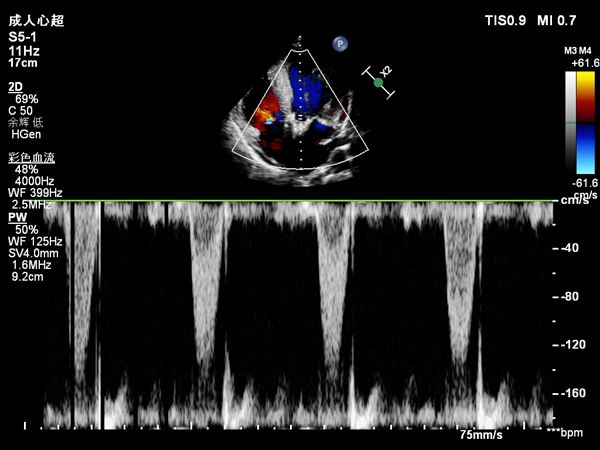

患者男性,61岁,1月余前活动后胸闷、气短,渐进加重伴夜间气喘不能平卧、咯血。曾行胸部CT示:两肺渗出性病变,两肺门增大;双侧胸腔少量积液;心脏彩超示:全心增大,左心为著,升主动脉增宽;左心收缩功能减低,左室后壁及侧壁运动幅度减低;主动脉瓣狭窄(中度);肺动脉高压(中度);冠脉造影示:前降支近中段节段性狭窄伴钙化,狭窄最重60%。曾诊断为“扩张型心肌病”,虽经利尿、逆转心肌重塑等治疗,仍因胸闷、气喘缓解不明显反复住院。心血管病院TAVR团队王新宏副主任医师接诊患者后考虑患者心脏射血分数0.31,存在因心功能差低估主动脉瓣狭窄可能,特请我院B超室韩东刚副教授为患者行小剂量多巴酚丁胺负荷试验:用药前每搏量35ml,Vmax:288cm/s,maxPG 33mmHg,meanPG20mmHg;多巴酚丁胺至15μg/min/kg:每搏量45ml,Vmax:478cm/s,maxPG 91mmHg,meanPG54mmHg,主动脉瓣口面积0.8cm2。患者心衰的罪魁祸首:低流速低跨瓣压差的主动脉瓣重度狭窄。患者心功能极差,如行开胸换瓣手术风险很高,在家属充分信任下决定行经皮主动脉瓣置换术。